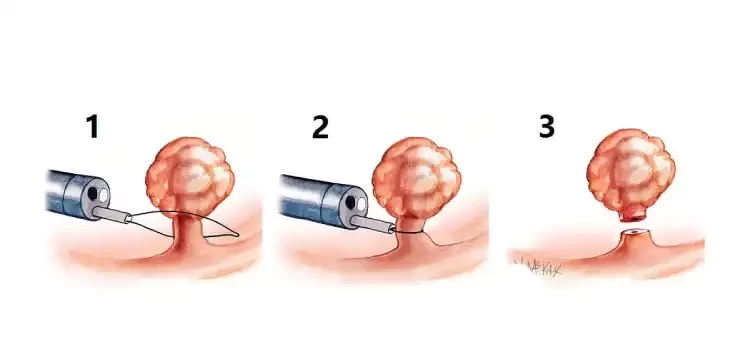

برای پولیپهایی با اندازه بیش از ۵ میلیمتر، پولیپکتومی با عبور یک حلقه سیمی از داخل کولونوسکوپ انجام میشود تا پایه پولیپ را احاطه و محکم بگیرد. سپس با کمک الکتروکوتریزاسیون، پولیپ بهطور ایمن برداشته میشود.

در تصویر زیر، میتوانید نحوه گیر انداختن و برداشتن پولیپهای بزرگتر از ۵ میلیمتر را مشاهده کنید.